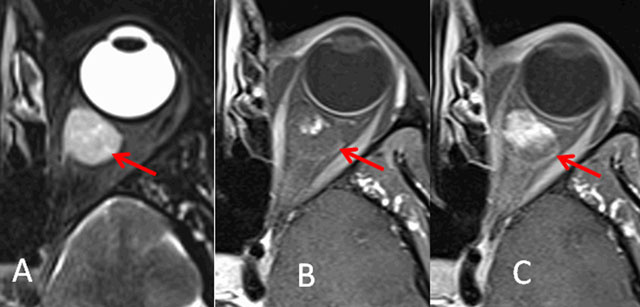

Among the intra- or extraconal lesions, cavernous hemangioma (the most frequent lesion encountered) shows a high signal on T2-weighted sequence, a progressive enhancement heterogeneous then homogeneous, (Figure 1). Orbital varix appearance may be challenging. Variation in the exophthalmos depending on the position of the patient is the diagnosis clue. Imaging protocol needs an acquisition, the patient being in prone position. Lesions of the orbital walls such as metastases, osteomeningiomas and fibrous dysplasia are the common diagnosis.

Figure 1

Cavernous hemangioma. Axial T2-weighted (A) and fat-saturated T1-weighted imaging with injection: immediate (B) and delayed (C).